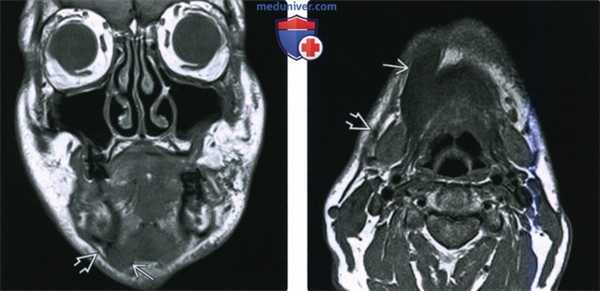

(Слева) МРТ Т1ВИ в аксиальной проекции, пациент, которому ранее проводилось лечение по поводу плоскоклеточного рака носоглотки. Костный мозг в правой ветви нижней челюсти замещен опухолевой тканью, на уровне отверстия нижней челюсти также определяется патологическая ткань, появление которой связано с распространением опухоли по нижнечелюстному нерву. Обратите внимание на нормальный костный мозг левой ветви нижней челюсти, который имеет гиперинтенсивный сигнал.

(Справа) МРТ Т1ВИ в аксиальной проекции, этот же пациент. Периневральное распространение опухоли по нижнечелюстному нерву с облитерацией жировой клетчатки жевательного пространства.

(Слева) МРТ Т1ВИ с КУ, коронарная проекция, этот же пациент. По нижнечелюстному нерву опухоль распространяется в овальное отверстие и тройничную полость. Также опухоль прорастает латеральнее, в твердую мозговую оболочку средней черепной ямки.

(Справа) КТ с КУ в аксиальной проекции, этот же пациент. В области правого отверстия нижней челюсти определяется накапливающая контраст опухоль. В жевательном пространстве видны участки аномального накопления контраста вдоль волокон нижнечелюстного нерва.